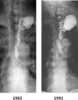

Thoracic duct cyst